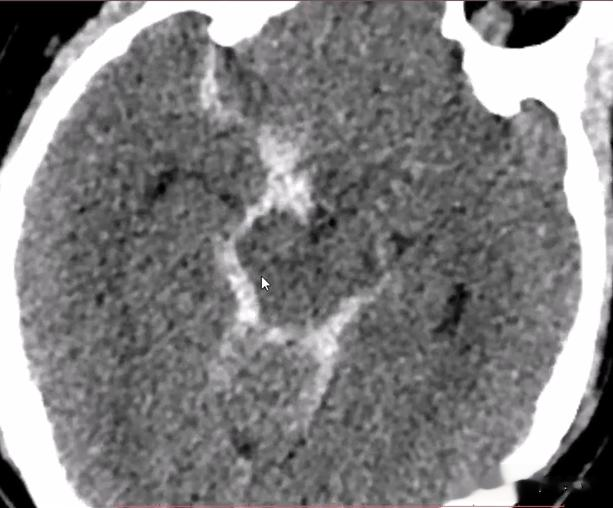

CT表现: 1.直接征象:为脑沟、脑池、脑裂密度增高 。 前动脉破裂 , 血液主要集聚于视交叉池、侧裂前部;大脑中动脉破裂 , 血液主要集聚于一侧侧裂 。

【动脉瘤|48岁女性,外伤后头痛剧烈,头颅CT发现了什么危急重症?】2.间接征象:脑积水、脑水肿、脑梗死、脑内血肿、脑室内积血、脑疝等 。 蛛网膜下腔出血位置常提示动脉瘤存在的部位 , 大脑外侧裂出血常提示大脑中动脉分叉处动脉瘤;大脑纵裂前部、视交叉周围出血提示前交通动脉瘤或前动脉瘤;脚间池、环池出血提示后交通动脉瘤或基底动脉瘤顶端动脉瘤;鼻咽或鼻腔出血提示虹吸部动脉瘤 。

蛛网膜下腔出血:右侧大脑半球部分脑沟高密度影填充